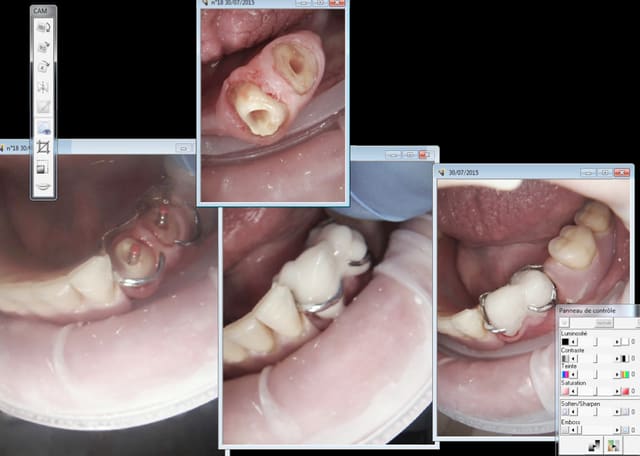

Par contre j'ai essayé le clip flow pour protéger l'entrée des canaux lors de la réalisation pré endo ( endo en 2 temps because urgence) autant ca marche bien pour les onlays autant c'est la galère à virer dans ce cas. -)))))

C'est à moitié mou le r25 passe à travers heureusement ! -))))

Ta reconstitution pré endo tu l'as fait avec quel compo sur les 3 que tu montres ?

C'est la meme.

J'ai utilisé le peak universal bond ( coltène) seul ( sans etching en plus !) puis estelite flow quick pour la base et estelite posterior pour monter les parois. C'est le collage qui cède pas le compo tu fais ca avec un SAM 1 ca pète, pour te donner le niveau d'adhésion de ces merdes. -)))